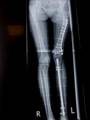

Follow Up

Left tibia lengthening with fixator in place

Lengthening tibia on Xrays in progress

Lengthening proceeding

Converted to immediate exchane nail after 65mm lengthening